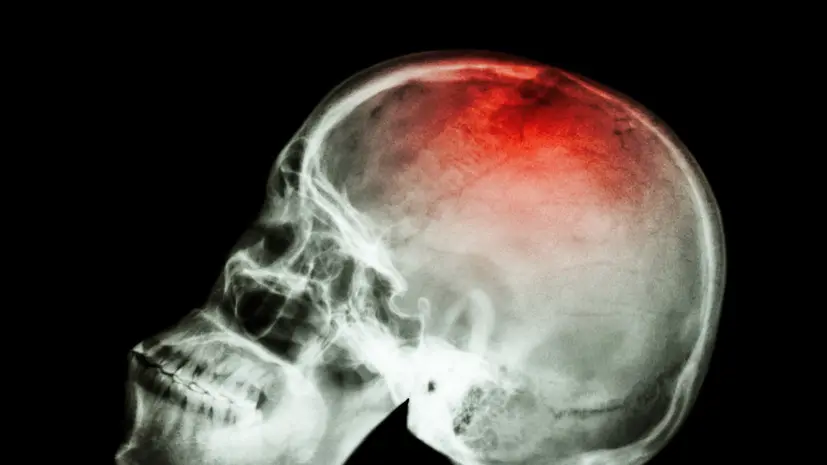

Риск развития инфаркта и инсульта достигает пика у людей старше 60-65 лет, подчёркивают кардиологи.

Для старшей возрастной категории именно болезни сердца и сосудов остаются основной причиной госпитализаций и летальных исходов.

У младших групп населения инфаркт или инсульт значительно чаще провоцируются такими факторами, как курение, сахарный диабет и тяжёлая гипертензия.